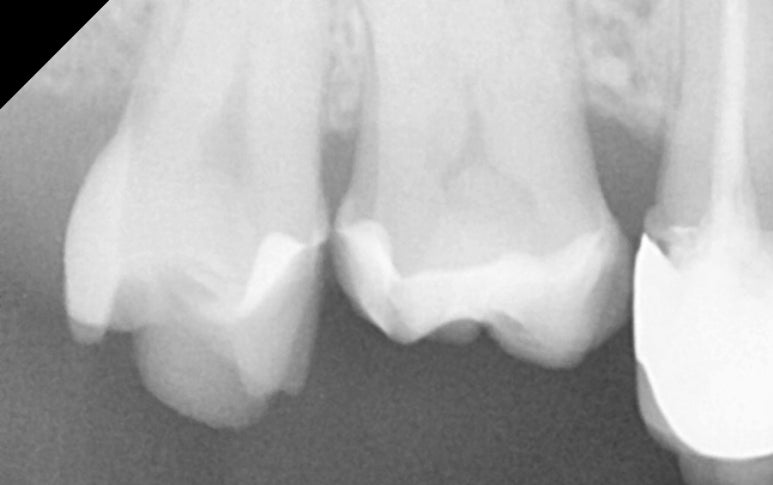

25.11.11 레진 코팅 후 엑스레이 사진

약 일주일 뒤,

기공소에서 정교하게 제작된

세라믹 수복물이 도착했습니다.

25.11.19 접착 준비

다시 한번

러버댐을 장착한 상태에서 정밀하게 접착을

마무리해 드렸습니다.

25.11.19 접착 후

25.11.19 접착 후 엑스레이

25.11.19 교합조정까지 마친 후